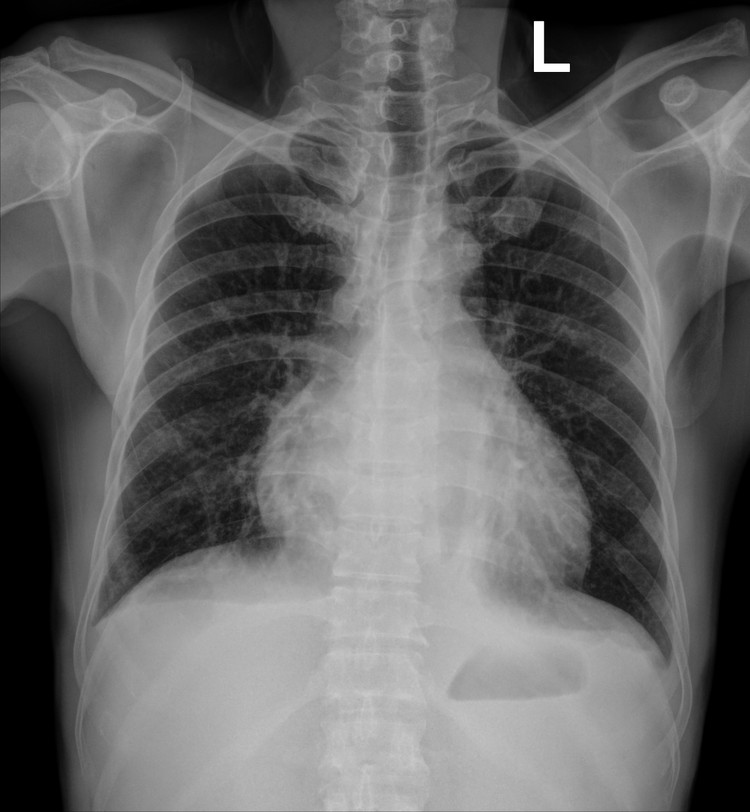

Vào viện, người bệnh được làm xét nghiệm máu và tủy, được chẩn đoán Bệnh bạch cầu cấp dòng tủy (AML-M6) kèm nhiễm trùng tiết niệu, rối loạn đông máu. X-quang ngực chụp buổi sáng cho thấy hai trường phổi sạch, tràn dịch màng phổi nhẹ, nghĩa là phổi lúc đó hoàn toàn “trong”.

ton-thuong-phoi.jpg

Phim chụp Xquang phổi của bệnh nhân C.Đ.C (21/10) - Ảnh BVCC